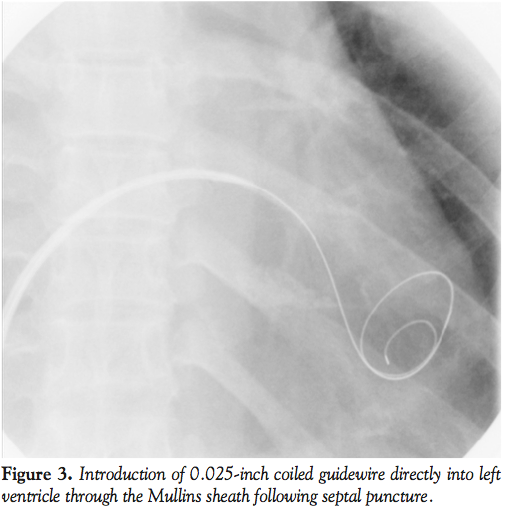

A 45-year-old woman presented with severe symptomatic mitral stenosis with mitral valve orifice area of 1.0 cm2 at cusp level and 0.4 cm2 at chordal level (Figure 1). The submitral apparatus was extensively diseased with thickening and fusion (Figure 2). Initially balloon mitral valvotomy (BMV) was attempted by over-the-wire technique described by the authors.1 In this technique, a deliberate low septal puncture is made and the 0.025-inch coiled guidewire is directly placed in the left ventricle (LV) (Figure 3).

Subsequently, a BMV balloon is passed over this wire and inflated. Because of severe submitral disease, there was resistance to the entry of the balloon catheter into the LV and the entire assembly backed out into the left atrium (Figure 4). Subsequently, we made several futile attempts to enter the LV.